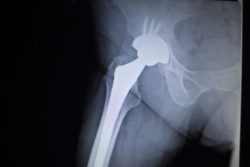

X-ray scan image of hip joints with orthopedic hip joint replacement implant head and screws in human skeleton in blue gray tones. Scanned in orthopedics traumatology surgery hospital clinic.A patient who allegedly suffered severe side effects about which they were never warned has recently filed an M2A-Magnum Hip Replacement lawsuit against the maker of the allegedly defective hip, Biomet.

In 2009, the plaintiff in this M2A-Magnum Hip Replacement lawsuit underwent a left total hip arthroplasty surgery with the metal on metal Biomet device. Symptoms including dislocation, component loosening, severe pain, lack of mobility and metallosis, allegedly affected the patient and ultimately led to severe injury.

According to the M2A-Magnum Hip Replacement lawsuit, the socket and ball bearings making up the hip joint lead to debris being accumulated in the body over time. This can spread to the patient’s surrounding tissue and bone, and can lead to unnecessary pain and suffering, and a number of other severe side effects.